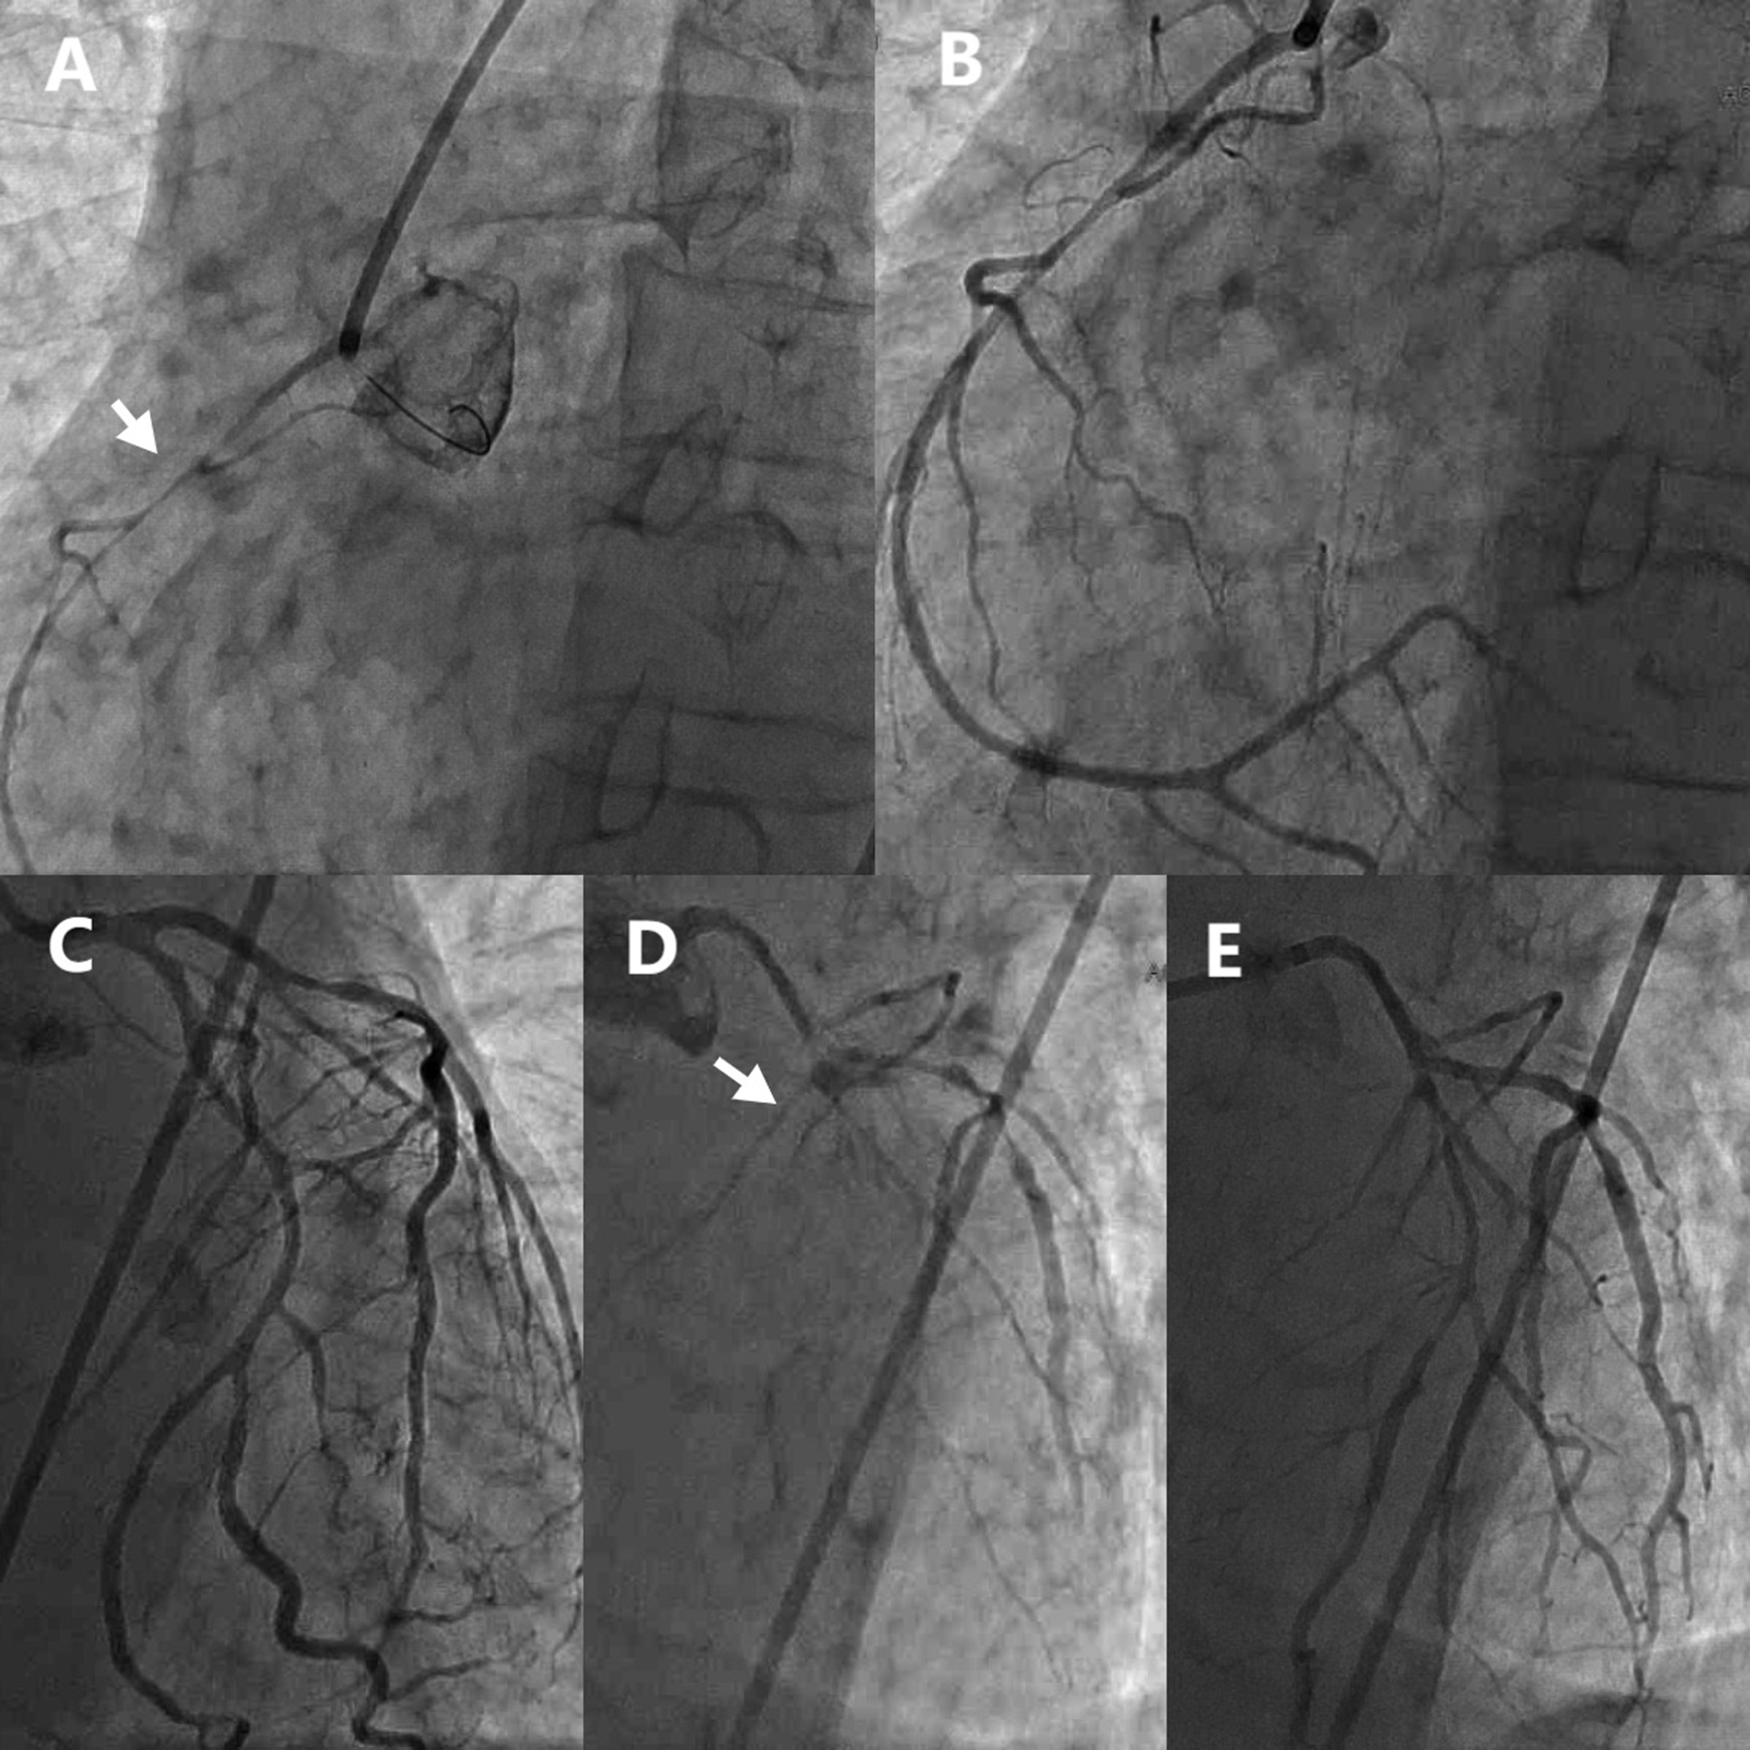

The initial left coronary angiography revealed no significant stenosis in the left main trunk, an 85% stenosis in the mid-segment of the left anterior descending (LAD) artery, and a 40% stenosis in the mid-segment of the circumflex (LCx) artery, with TIMI 3 flow. Subsequent right coronary angiography encountered technical difficulties due to inadequate catheter engagement. Utilization of a JR4.0 guiding catheter disclosed a slender, elongated proximal right coronary artery (RCA) with approximately 80% stenosis. Administration of intracoronary nitroglycerin (NTG) led to a significant resolution of stenosis, thereby confirming coronary artery spasm as the underlying mechanism.

In light of the discordance between the presumed RCA culprit lesion and the initial ECG findings, a repeat left coronary angiography was conducted. This procedure demonstrated a no-reflow phenomenon in the proximal LAD (TIMI 0 flow) and an 85% stenosis in the proximal LCx. The injection of intracoronary NTG (200 µg) into the left coronary system restored full LAD perfusion (TIMI 3 flow), thereby confirming DMV-CAS as the etiology of the LAD lesion. The proximal LCx stenosis improved to 50% post-spasm relief, verifying the coexistence of underlying atherosclerotic plaque (Figure 2).

Figure 2

Emergency coronary angiography showed diffuse spasm of multiple coronary arteries. (A) RCA before NTG administration. (B) RCA after NTG administration. (C) Initial LCA imaging findings. (D) LCA second imaging results. (E) LCA after NTG administration. RCA, Right coronary artery; LCA, Left coronary artery; NTG, Nitroglycerin.